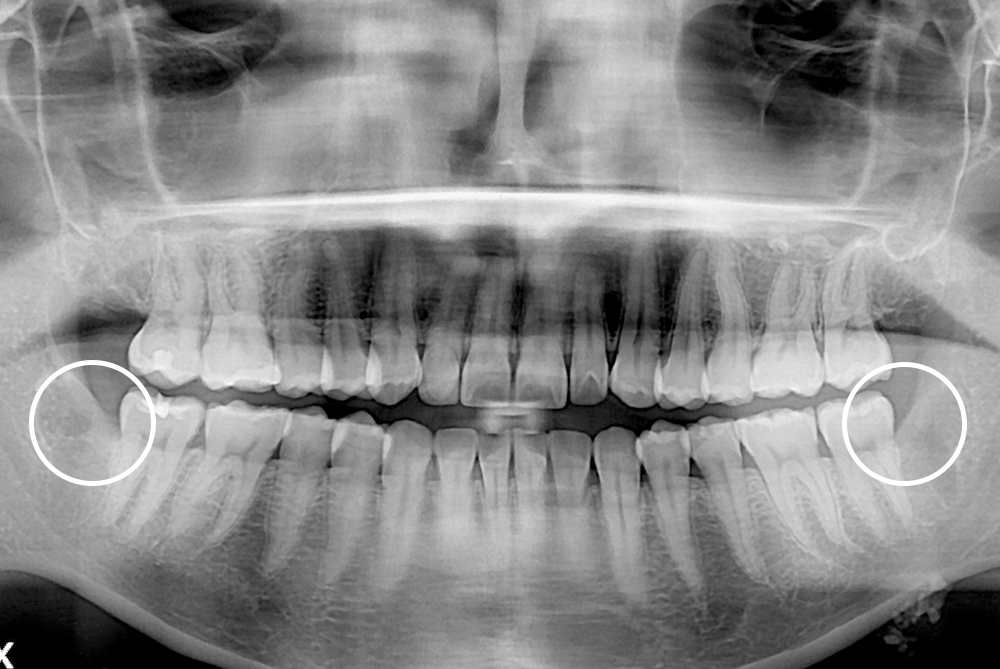

[사랑니] 매복 사랑니 발치

치료전 : 2021-12-15

세종치과는 구강악안면외과학 박사이신 원장님이 발치하는 치과입니다.